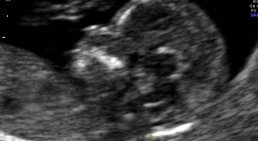

Der Ultraschall und die Schwangerschaftsbetreuung sind mir ein besonderes Anliegen.

Zusätzliche Untersuchungen wie Nackentansparenzmessung, Combined Test, Präeklampsiescreening, NIPT (Nicht Invasiver Pränatal Test) und auch Organscreening (Feindiagnostik) werden auf Wunsch von mir durchgeführt.

Als Inhaber der ÖGUM Stufe II als auch durch die jährliche Zertifizierung der FMF London für Firsttrimester Screening kann ich Ihnen Ultraschall in höchster Qualität anbieten.